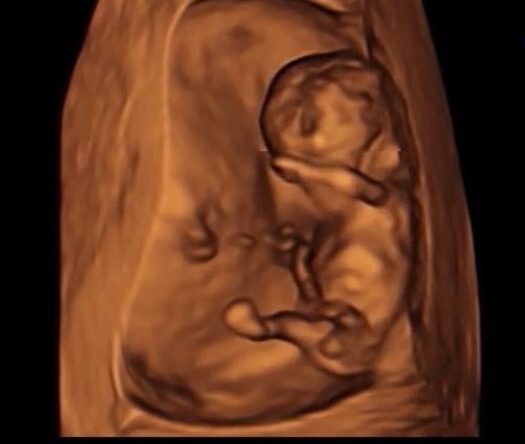

初めてR先生に動画を送り、判定してもらったのは10w6d。

この時点では7割男児との結果でした。

↓実際に1回目で送ったエコー画像がこちらです。

まだ初期のため確定ではないものの、ナブの角度から男の子寄りとの判定。